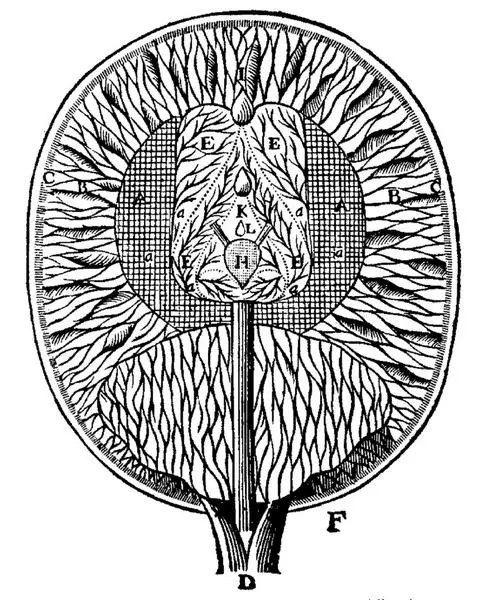

На рисунке Р. Декарта шишковидная железа, или эпифиз, обозначена буквой Н

В организме позвоночных животных, в том числе и у человека, синтезом мелатонина занята шишковидная железа, или эпифиз. Но прежде чем установить этот, хорошо известный сегодня, факт, ученые провели многочисленные эксперименты, порой весьма тонкие и сложные.

И только в начале XX века австрийский невролог О. Марбург предположил, что эпифиз синтезирует и выделяет специфическое соединение, которое оказывает непосредственное влияние на работу гипоталамуса и, как следствие – на развитие и функционирование развитие репродуктивной системы.